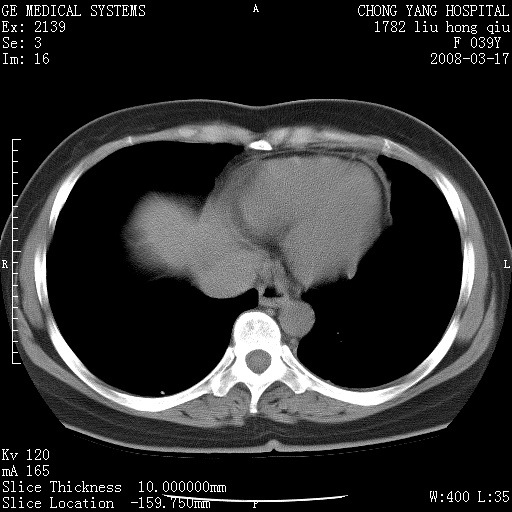

以下是引用yangxue121在2008-5-31 20:24:00的发言:[br]考虑多发胸膜间皮瘤[br]左侧少量胸腔积液[br]肝脏密度不均

以下是引用王仕学在2008-5-31 20:10:00的发言:[br]考虑胸膜间皮瘤。

以下是引用长城干红在2008-5-31 21:42:00的发言:[br]肝脏密度不均,建议增强扫描,胸膜下多发结节,考虑为胸膜来源的原发肿瘤或转移瘤。